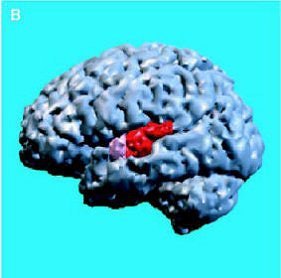

| Above, regions of interest (ROI) examined in MRI study of patients with first-episode schizophrenia or affective psychosis and normal comparison subjects. Top (A) is a 1.5-mm coronal slice of the temporal lobe; the ROI used to evaluate the temporal structures are outlines. The gray matter of the superior temporal gyrus is shown in red (subject left) and green (subject right); more medially, the amygdala-hippocampal complex is shown in orange (left) and blue (right) with the parahippocampal gyrus underneath in pink (left) and purple (right). Below, a left lateral view of a 3D reconstruction of the cortical surface with the anterior superior temporal gyrus (light pink) and posterior superior temporal gyrus (red). |